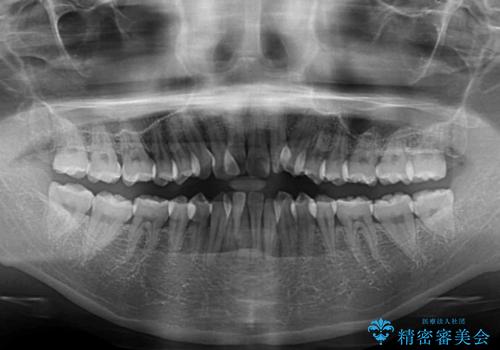

通常であれば、上下顎左右小臼歯各1歯の合計4本を抜歯しますが、歯肉退縮の著しい下顎前歯を抜歯して欲しいという患者様の強い希望により、上顎のみ左右小臼歯2歯を、下顎は前歯を1歯を抜歯することとしました。

抜歯する歯を変更したため奥歯の咬合はアンバランスとなりましたが、前歯は綺麗に整い、歯肉退縮も回避できました。